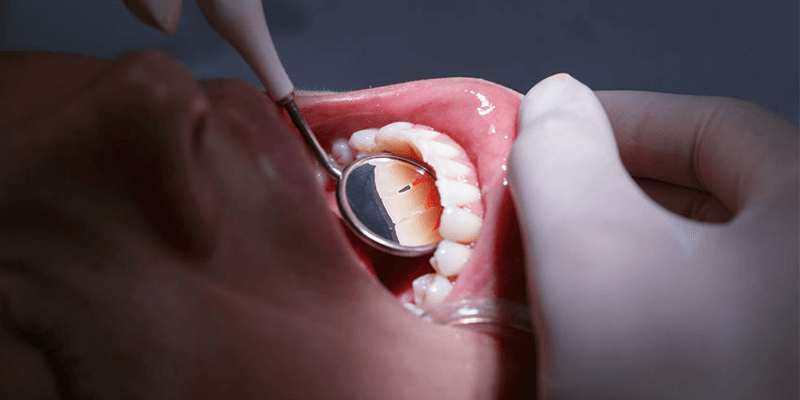

Zahnfleischerkrankungen und Zahnbehandlungen

Meist bemerkt man Zahnfleischerkrankungen selbst – beim Essen, während der Mundhygiene oder durch reine Berührung mit der Zunge oder der Zahnbürste. Eine Schwellung des Zahnfleisches und eine rote Verfärbung sind eindeutige Anzeichen einer Zahnfleischentzündung. Zum Vergleich: Ist das Zahnfleisch gesund ist es hell rosa in der Farbe. Am Besten lassen sich Zahnfleischerkrankungen durch eine ausgiebige und richtige Mundhygiene verhindern sowie behandeln. Die Bakterien aus der Nahrung setzen sich besonders gern an schlecht zugänglichen Stellen zwischen den Zähnen oder an den Furchen zwischen Zahnfleisch und -schmelz fest. Dort sondern sie Giftstoffe ab, die für die Erkrankungen des Zahnfleisches verantwortlich sind.

Die Reizungen werden vom Immunsystem des Körpers wahrgenommen und eine Bekämpfung in Form von einer Entzündung entsteht. Eine gründliche Reinigung der Zahnhälse und Zahnzwischenräume mit Bürste, Zahnseide und antiseptischen Mundwassern hilft hier nicht nur in der Vorbeugung – entgegen der üblichen Reaktion des Betroffenen, die entzündeten Stellen zu schonen, sollte besonders bei einer vorhandenen Entzündung verstärkt geputzt werden, um die Bakterien aus dem Mundraum zu entfernen. Grundsätzlich unterscheidet man drei auf einander aufbauenden Stadien bei Zahnfleischerkrankungen:

Die so genannte Gingivitis ist die erste Phase. Aufgrund von Zahnbelag und den darin enthaltenen Bakterien werden Giftstoffe ausgesondert. Diese reizen das Zahnfleisch, es schwillt an, rötet sich, schmerzt und blutet beim Zähneputzen oder beim abbeißen harter Speisen. In diesem Stadium lässt sich die Erkrankung durch ausgiebige Mundhygiene, unterstützenden Mundspülungen und durch Hilfe des Arztes noch sehr gut behandeln und führt zur vollständigen Genesung, da der Kieferknochen und der Zahnhalteapparat noch nicht befallen sind. Diese Phase wird meist von Mundgeruch begleitet, der durch die Bakterien ausgelöst wird.

Wird die Gingivitis nicht behandelt, entsteht eine Parodontitis. Das Zahnfleisch zieht sich zurück und gibt damit den Bakterien die Möglichkeit, noch tiefer unter die Zähne und in die Zahntaschen vorzudringen. Das Zahnfleisch selbst, das Bindegewebe und der Knochen werden in diesem Stadium irreversibel (ohne die Möglichkeit der Rückbildung) geschädigt. Es bilden sich bis zu 10mm tiefe Furchen zwischen Zahnfleisch und Wurzeloberfläche des Zahnes, die immer schwieriger zu reinigen sind. Ein Zahnarztbesuch ist nun nicht mehr zu verhindern. Der Zahnarzt hilft, die Entzündung einzudämmen und eine weitere Ausweitung zu verhindern. Hier ist nun höchste Gefahr geboten, dass der Kieferknochen aufgelöst wird, was unweigerlich zum Verlust der Zähne führt.

Putzen Sie die Zähne mit einer weichen Zahnbürste, die über einen druckverhindernden „Knick“ verfügt. Kreisförmige Putzbewegungen sind hierbei besser als gerade, um die Bakterien über den Zahnschmelz abzutransportieren statt sie auf die nebenliegenden Zähne zu verteilen. Fertige, antiseptische Mundwasser oder Tees mit Salbeiauszügen, Kamillenanteilen oder Myrrhe beruhigen das Zahnfleisch und hemmen die Reizungen. Eine professionelle Zahnreinigung beim Zahnarzt ihres Vertrauens in Kombination mit einer Behandlung der vorhandenen Entzündung und einer Röntgenaufnahme, um einen Befall des Kieferknochens auszuschließen, ist jedoch die perfekte Reaktion bei einer anhaltenden Zahnfleischerkrankung.